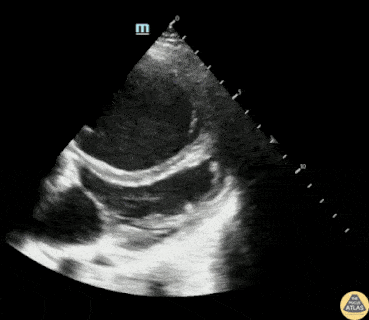

30s F with PMH IVDU and prior endocarditis s/p tricuspid valve repair presented with fever, hypotension, and dyspnea. On RUSH evaluation, this cardiac image was acquired, showing significant RV dilation with bowing of the septum into the LV. The prosthetic tricuspid valve is shown here, but without color doppler, evaluation of the valve patency is limited. Formal TTE showed a patent tricuspid valve however with moderate to severe tricuspid regurgitation, likely explaining the severe RV overload. Dr. Michael Duerson, PGY4 Denver Health Residency in Emergency Medicine